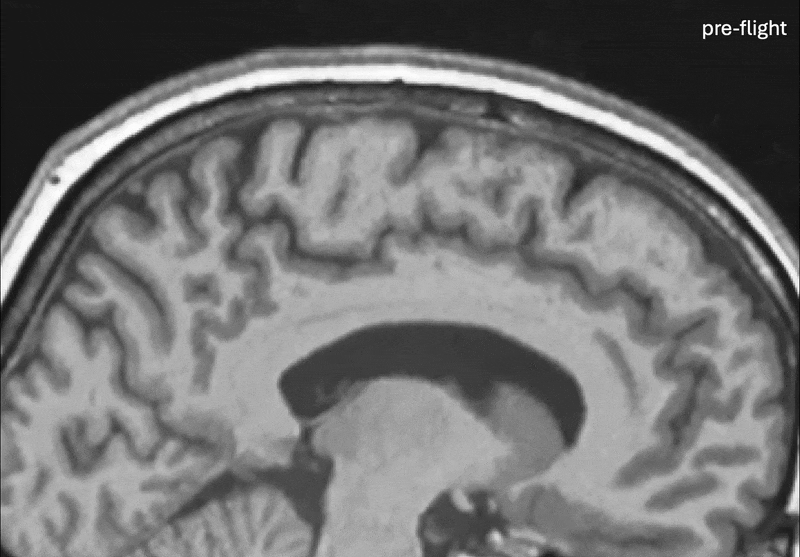

Astronauts’ Brains Move and Rotate During Extended Spaceflight and Apparently Viruses and Bacteria Evolve Differently in Space.The Week in Space: Artemis II Readies for Crewed Lunar Mission, China Submits ITU Filings for 193,000 Satellites, NASA Plans to Deploy A Lunar Nuclear Reactor by 2030 and US War Department Invests $1B in L3Harris. ESA and China Resume High‐Level Space Talks in Paris After Nearly a Decade, Plus: York Space Prepares for an IPO, Slingshot Wins Space Force Contract, Luxembourg’s Hydrosat, India's Aule, Japan's Interstellar Technologies, SkyFi and Think Orbital Raise Funding, Parsons Acquires Altamira, and More.